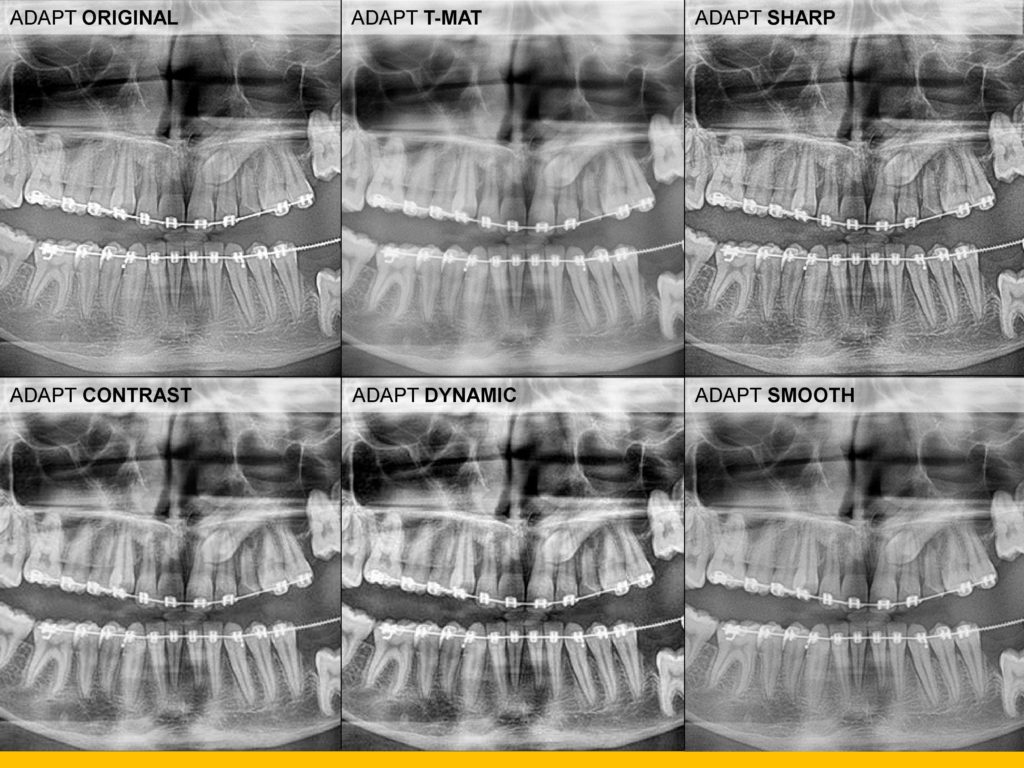

- Uz najnovije algoritme za obradu softvera, CS 8100 minimizira sjene kralježnice i proizvodi jasne, oštre digitalne slike koje su spremne za pregled gotovo odmah.

- Snažni filtri bez artefakata povećavaju kontrast i oštrinu jednim klikom